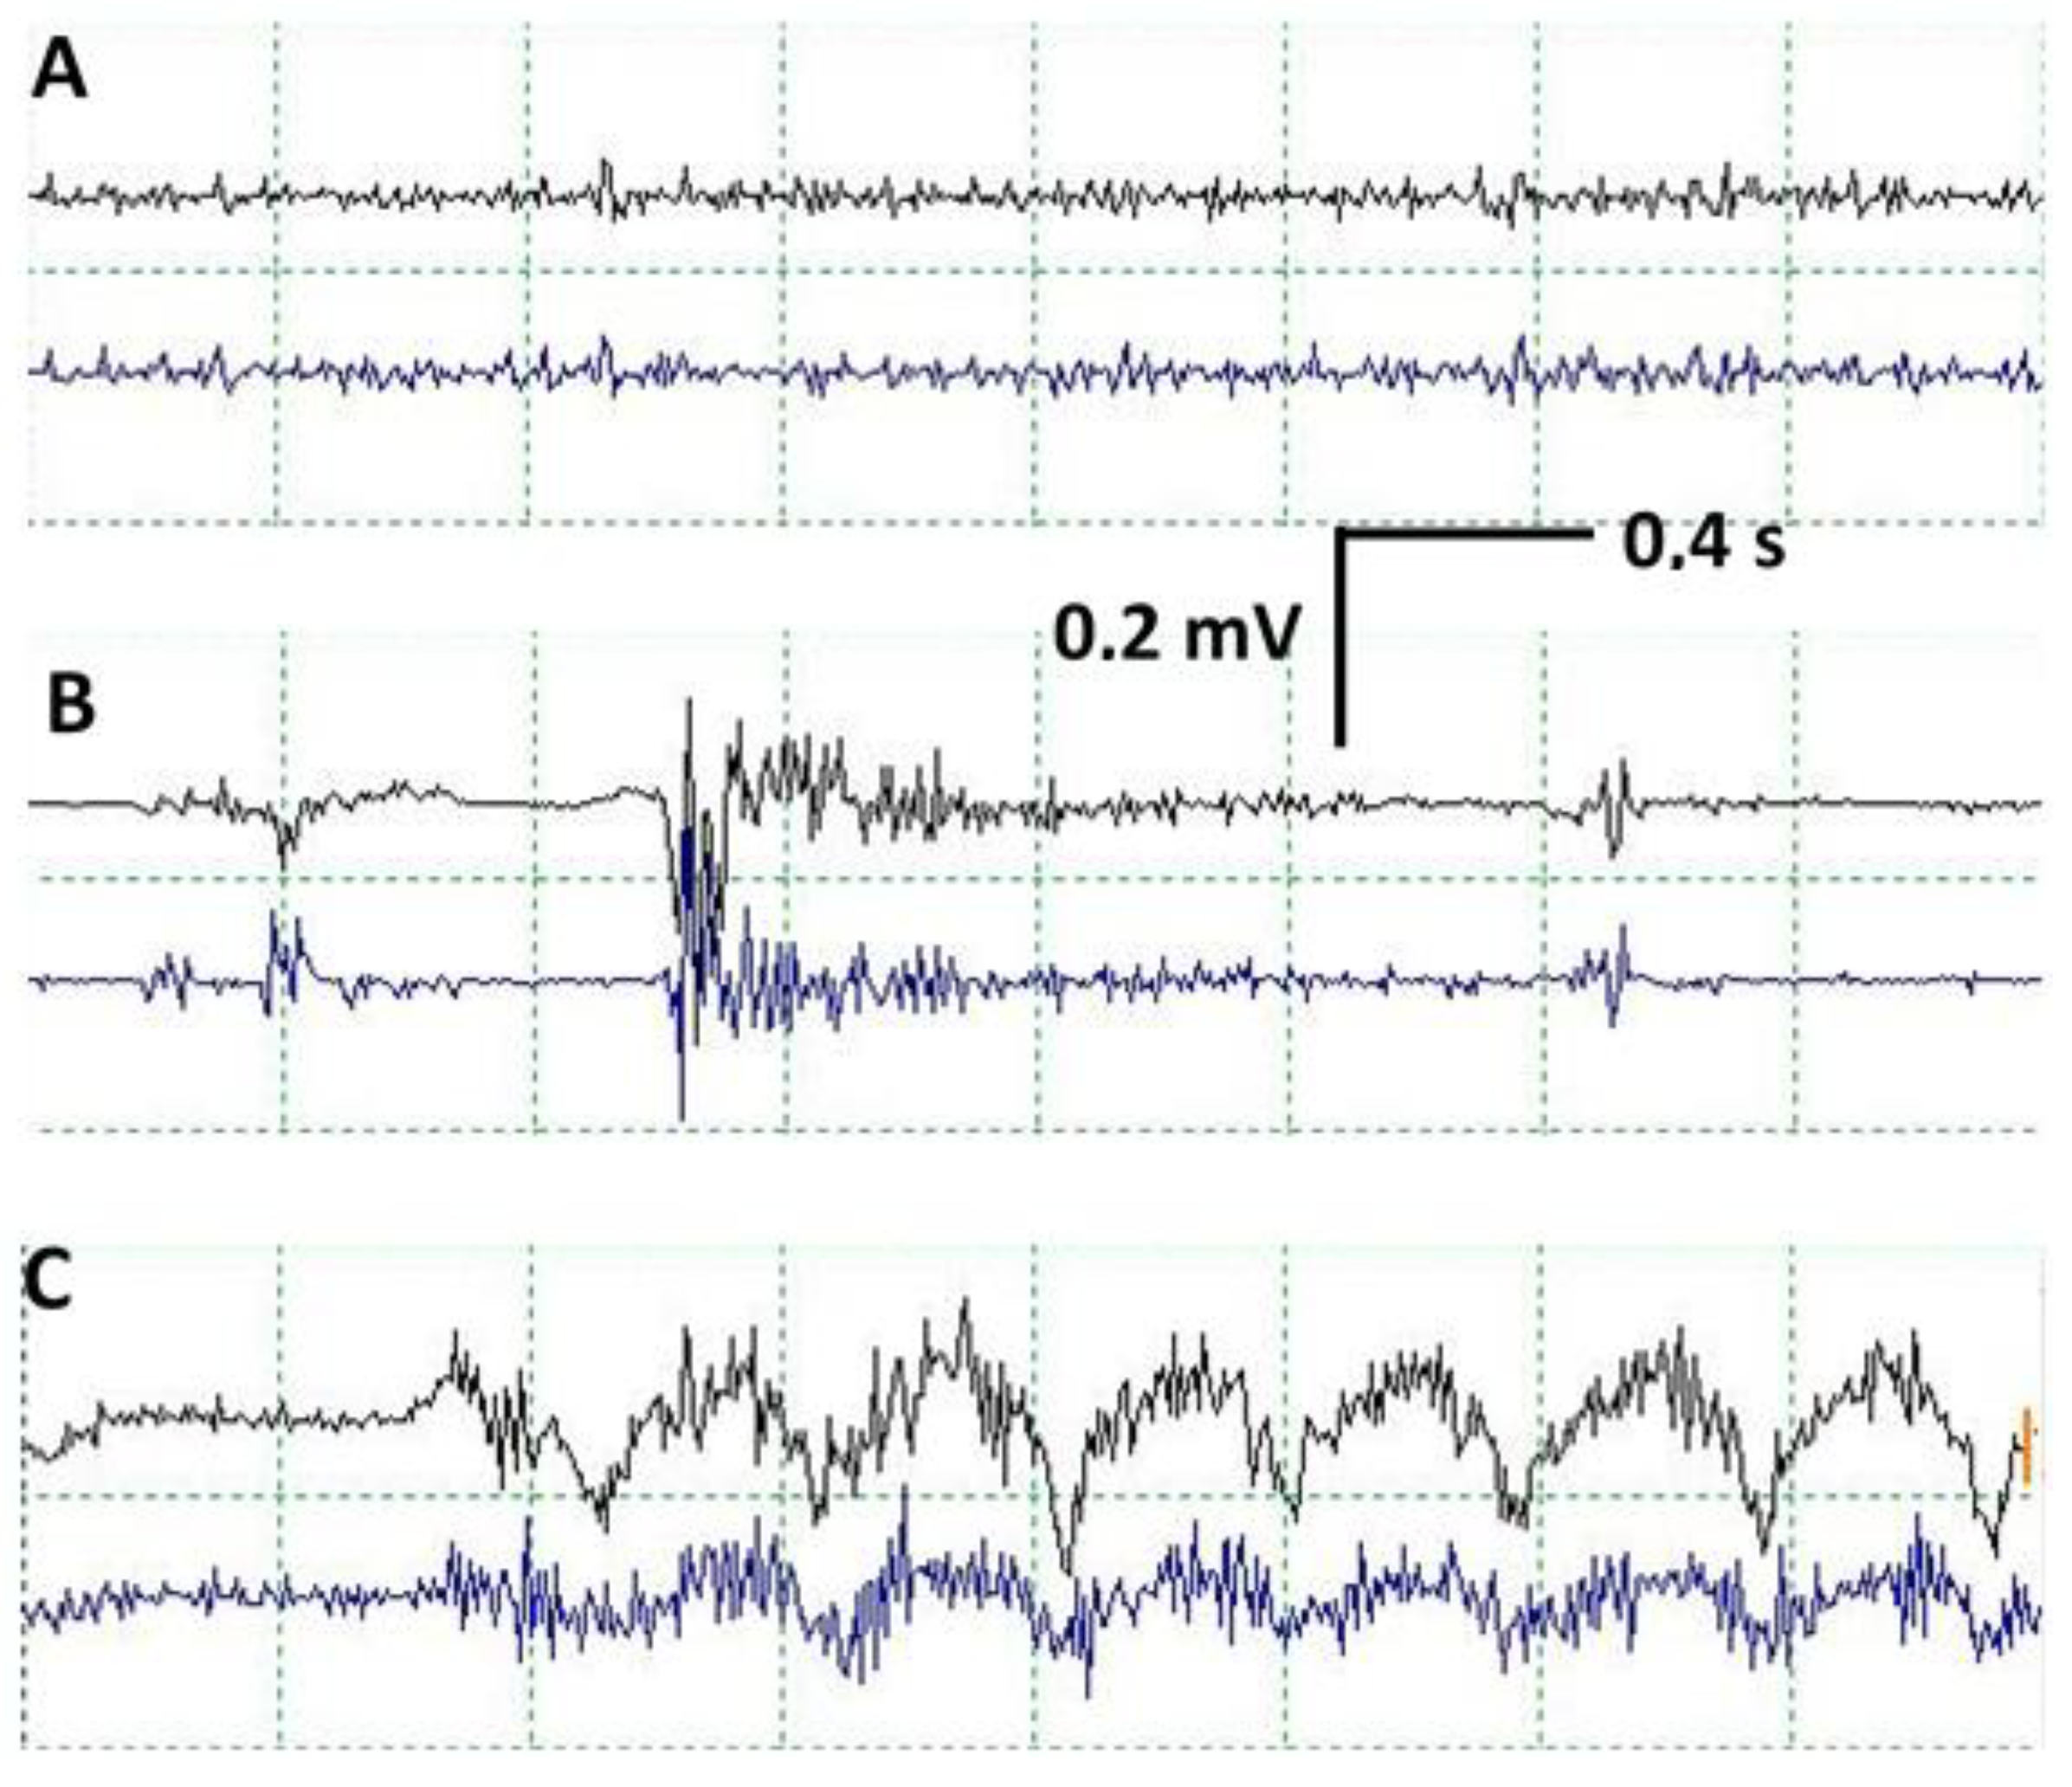

cEMG was performed for all patients, recording a continuous basal activity of low amplitude in relation to the muscle tone maintained by the VC. Superimposed EMG discharges of variable duration and intensity have been recorded in all patients in relation to RLN manipulation, mainly using traction. When this occurs, it should always be reported immediately to avoid possible nerve injury. Vagal stimulation should also be performed to check how conduction through the RLN is maintained, thereby ruling out any possible injury. We have not seen any cases of nerve injury associated with discharges in cEMG if it is not linked to abnormal changes in CMAP. Another type of activity that we recorded are movement artifacts due to the displacement of the larynx during thyroid dissection (Figure 4).

Figure 4.

In each figure, the upper trace corresponds to the recording in the right vocal cord, and the lower trace corresponds to the left vocal cord. (A) Normal EMG recording in vocal cords. Continuous activity due to tonic contraction of vocal cords. (B) EMG discharge related to RLN manipulation. (C) Movement artifact due to displacement of the larynx during thyroid dissection, which can provoke changes in the morphology of the CMAP in VC due to movement of the orotracheal tube.